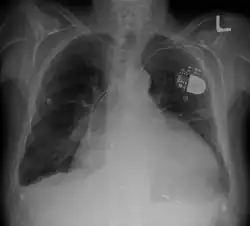

- Chest X-ray: X-ray images help to visualize the condition of the lungs and heart. If the heart is enlarged on an X-ray, other tests will usually be needed to find the cause. A useful measurement on X-ray is the cardio-thoracic ratio, which is the transverse diameter of the heart, compared with that of the thoracic cage.[30] These diameters are taken from PA chest x-rays using the widest point of the chest and measuring as far as the lung pleura, rather than lateral skin margins. If the ratio is greater than 50%, pathology is suspected.[31] The measurement was first proposed in 1919 to screen military recruits. A newer approach to using these x-rays for evaluating heart health takes the ratio of heart area to chest area and has been called the two-dimensional cardiothoracic ratio.[32]

- Pacemaker: Coordinates contractions between ventricles. In people at risk of arrhythmias, drug therapy or an implantable cardioverter-defibrillator (ICD).

- ICDs: Small devices implanted in the chest to monitor heart rhythm and deliver electrical shocks to control abnormal heartbeats. The devices can also work as pacemakers.